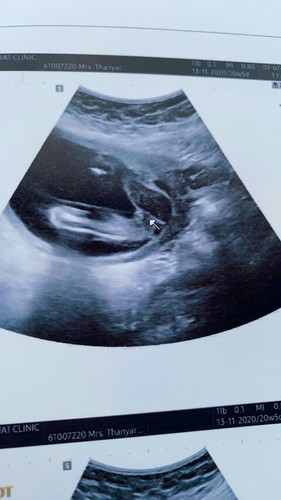

ดูตรงลูกศร หมอบอกเป็น ญ แต่ตอนแรกดูเหมือนไม่ใช่

ผู้หญิงจ้า